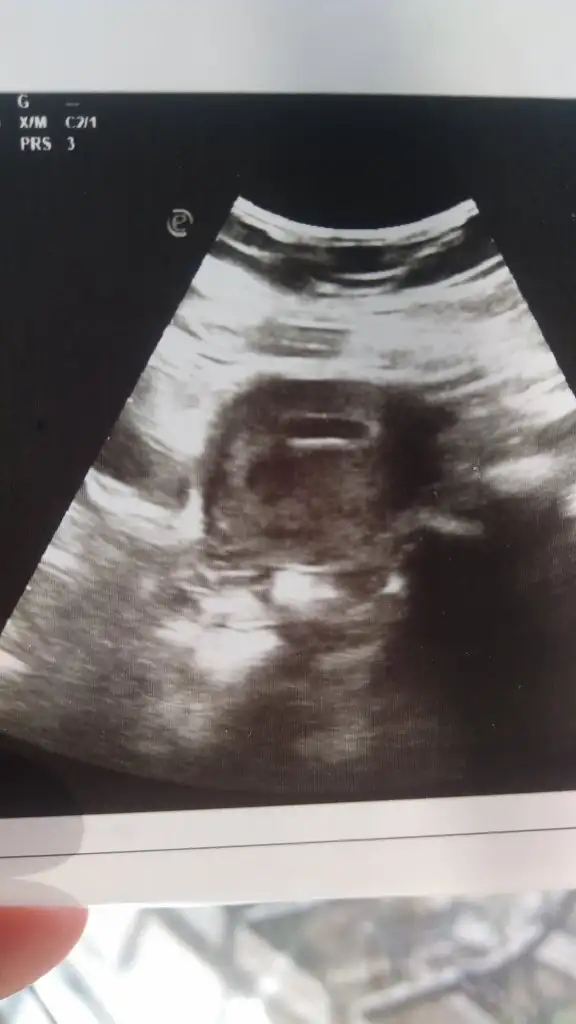

Kızlar kağıdımı yorumlayabilir misiniz yolk kesesi vs doktor 5 haftalık 10 mm dedi 2 hafta sonra kalp atışı için gel dedi başka bişey demedi

Eklentiler

• 20211130_114523.webp

20211130_114523.webp

16,7 KB · Görüntüleme: 214